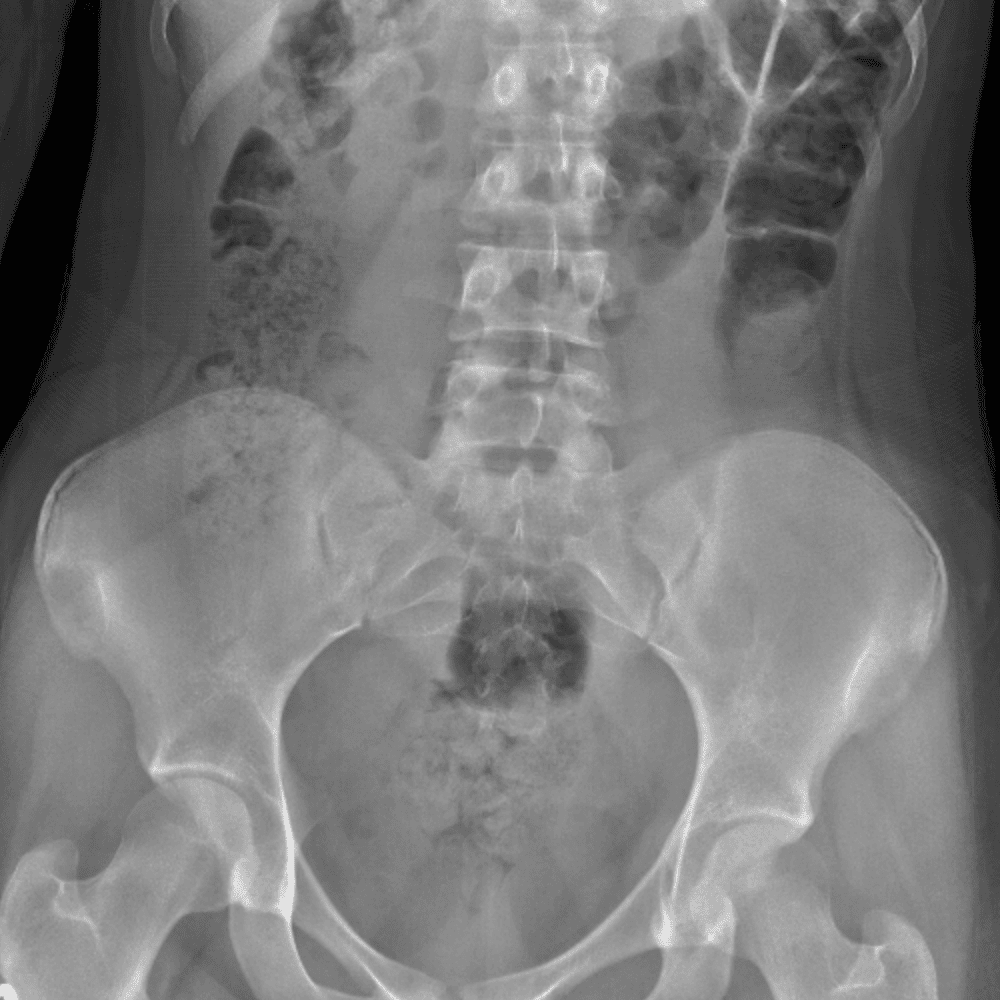

Peds Abdomen

Practice

Simulates call by including subtle or difficult cases and some normals.

30 cases